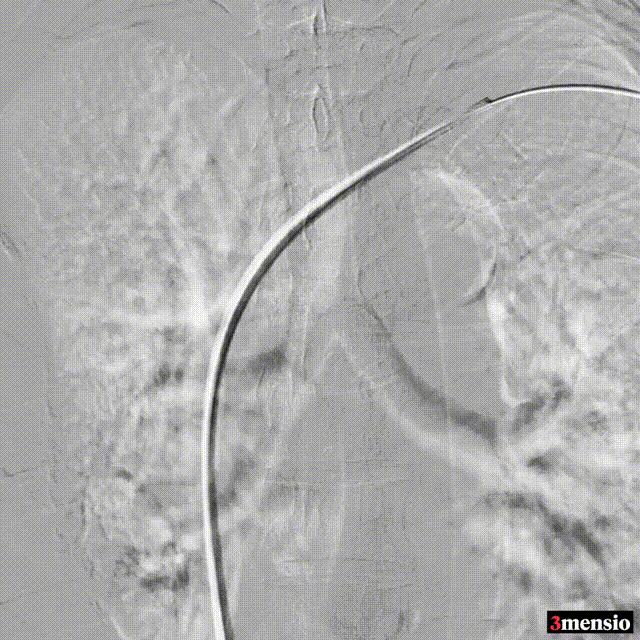

术中造影

图:术中造影

术后:支架定位困难,未能完全覆盖病变

图:术后